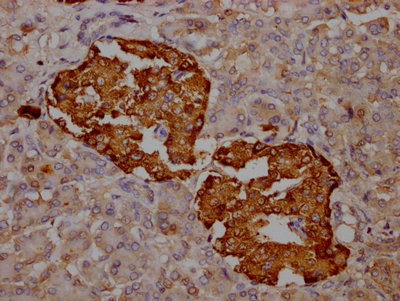

IHC image of CSB-RA588381A0HU diluted at 1:100 and staining in paraffin-embedded human pancreatic tissue performed on a Leica BondTM system. After dewaxing and hydration, antigen retrieval was mediated by high pressure in a citrate buffer (pH 6.0). Section was blocked with 10% normal goat serum 30min at RT. Then primary antibody (1% BSA) was incubated at 4℃ overnight. The primary is detected by a Goat anti-rabbit IgG polymer labeled by HRP and visualized using 0.05% DAB.

產品描述:CSB-RA588381A0HU TTR重組單克隆抗體是針對轉甲狀腺素蛋白(Transthyretin, TTR)開發的高特異性科研工具,適用于ELISA和免疫組化(IHC)實驗。TTR是一種由肝臟和脈絡叢分泌的運輸蛋白,主要參與甲狀腺素和視黃醇結合蛋白的轉運,其異常折疊與淀粉樣蛋白沉積疾病密切相關。本抗體通過重組表達技術制備,經ELISA和IHC雙重平臺驗證,在IHC應用中推薦使用1:50-1:200稀釋比例,能夠清晰識別石蠟包埋組織切片中的天然TTR蛋白,展現優異的組織定位特異性。其單克隆特性保障了不同實驗批次間的高度一致性,為研究TTR在代謝調控、神經退行性疾病中的功能機制,或探索淀粉樣纖維形成過程的分子基礎提供可靠支持。該產品適用于肝臟功能研究、淀粉樣變性病理模型分析以及蛋白質穩態調控等科研領域,特別針對神經系統和心血管系統的相關研究設計,為體外實驗提供精準的靶標檢測方案。

應用范圍:ELISA, IHC

Application Recommended Dilution IHC 1:50-1:200 -